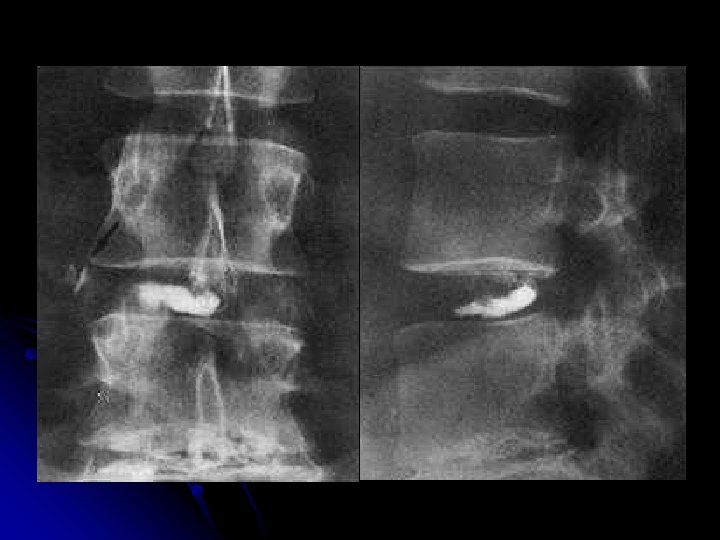

DISCOGRAPHIE lombaire+++

DISCOGRAPHIE